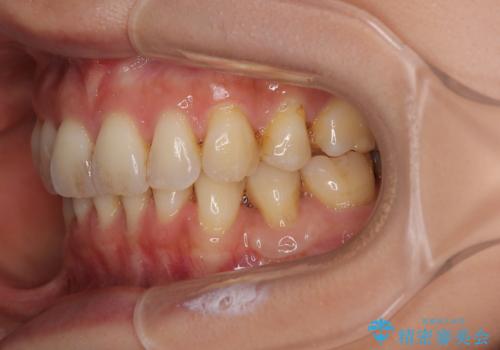

移植片には、極力角化歯肉が多く残るようにし、被覆するだけでなく、歯肉の厚みを増やし、角化歯肉を回復させることができました。